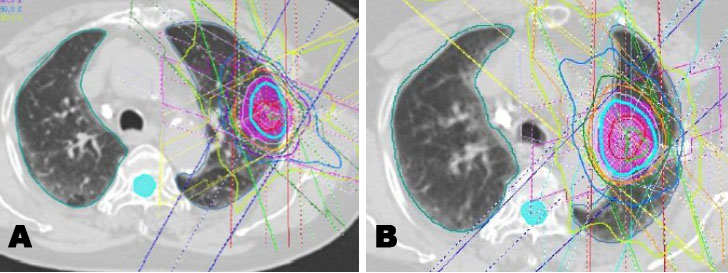

An 80-year-old woman was diagnosed with stage I (T1aN0M0) squamous cell carcinoma in left upper lobe (Figure 1A). She had a history of smoking and was being treated for liver cirrhosis. She received initial SBRT at an irradiation dose of 48 Gy in 4 fractions at the isocenter (Figure 2A). The maximal planning target volume (PTV) dose was 48 Gy. The mean lung dose (MLD) was 3.8 Gy, the volume of the lung receiving 5 Gy (lung V5) was 26%, and lung V20 was 7.5%. Follow-up examinations were conducted 1, 3, 6, 9, and 12 months after initial SBRT in the first year, and then every three months. Although the lung tumor temporarily shrank, two years and three months after initial SBRT, a new lesion, near the primary tumor, has developed in the same lobe (left upper lobe). Serial enlargement and increased uptake on fluorodeoxyglucose-positron emission tomography/computed tomography (FDG-PET/CT) were evident (Figure 1B and Figure 1C). The patient was clinically diagnosed with post-SBRT local recurrence or new primary lung cancer without pathological proof and, thus, received repeat SBRT. The repeat SBRT irradiation dose was 60 Gy in 10 fractions (Figure 2B), which was selected because local recurrence was in a central location. The maximal PTV dose was 60 Gy. Mean lung dose was 5.5 Gy, lung V5 was 20%, and lung V20 was 10%.

Figure 2: (A) Initial SBRT irradiation dose of 48 Gy in 4 fractions. (B) Repeat SBRT irradiation dose as a salvage option for local recurrence of 60 Gy in 10 fractions.